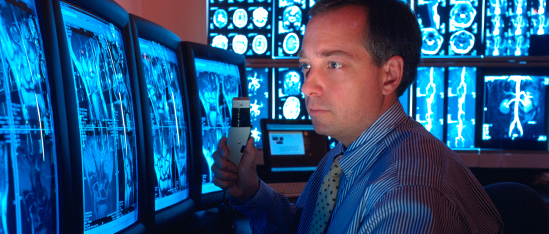

Radiology Associates of Northern Kentucky is the largest private-practice Radiology group in greater Cincinnati. Our caring physicians and staff are committed to providing compassionate care to our patients on a 24-hour basis at Greater Cincinnati's leading hospitals and imaging centers.

We pioneered the use of many technologies and procedures for diagnosing and treating disease that are common today. Our full range of services includes state-of-the-art Diagnostic Imaging, Interventional Radiology procedures, and minimally invasive treatments.

Vascular and Interventional Associates (VIA) provides complete clinical service for patients and referring physicians from the caring professionals who have been the area's leading specialists in vascular care, spinal care and other IR therapies since 1968.